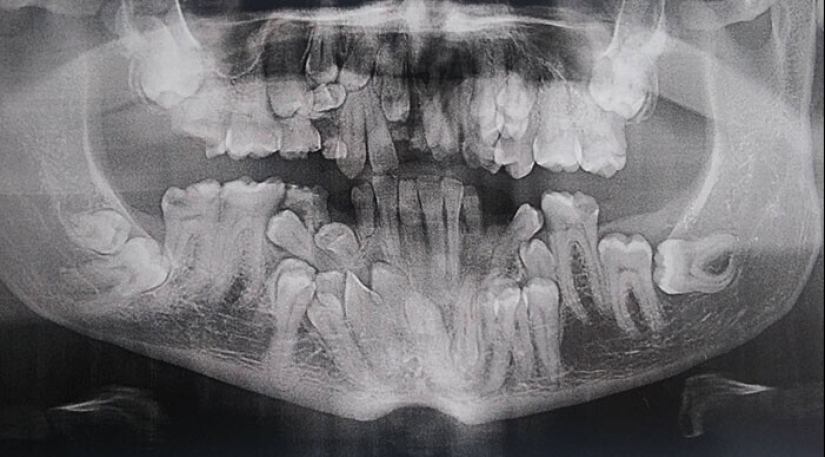

"Yo cleidocraneal desotos, o, si es más fácil, mi mandíbula un montón de extra "de repuesto" dientes"

"Soy un dentista, pero los rayos x de los niños de 6-12 años me asustan un poco todavía"